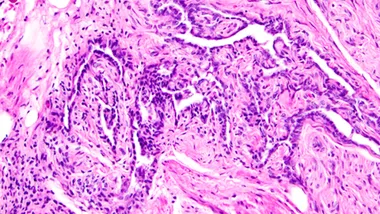

Команда дослідників на чолі з біологом Ділярою Анбарджі з Мічиганського університету провела фундаментальне дослідження, яке охоплювало експерименти на мишах. Науковці виявили, що ця структура є набагато складнішою та важливішою, ніж вважалося раніше. Rete ovarii являє собою своєрідну підковоподібну мережу трубочок, розташовану під яєчником у місці входження кровоносних судин та нервів.

Унікальність дослідження полягає в тому, що вчені застосували сучасні методи мас-спектрометрії та флуоресцентної мікроскопії, які дозволили детально вивчити внутрішню будову та функціональність цієї структури. Виявилося, що rete ovarii складається з трьох чітко визначених регіонів: внутрішньояєчникового (IOR), зовнішньояєчникового (EOR) та перехідного (CR).